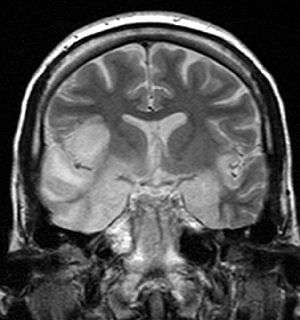

|

Coronal T2-weighted MR image shows high signal in the temporal lobes including hippocampal formations and parahippocampal gyrae, insulae, and right inferior frontal gyrus. A brain biopsy was performed and the histology was consistent with encephalitis. PCR was repeated on the biopsy specimen and was positive for HSV | |

Limbic encephalitis

Limbic encephalitis refers to inflammatory disease confined to the limbic system of the brain. The clinical presentation often includes disorientation, disinhibition, memory loss, seizures, and behavioral anomalies. MRI imaging reveals T2 hyperintensity in the structures of the medial temporal lobes, and in some cases, other limbic structures. Some cases of limbic encephalitis are of autoimmune origin.[12]

- Brain scan, done by MRI, can determine inflammation and differentiate from other possible causes.